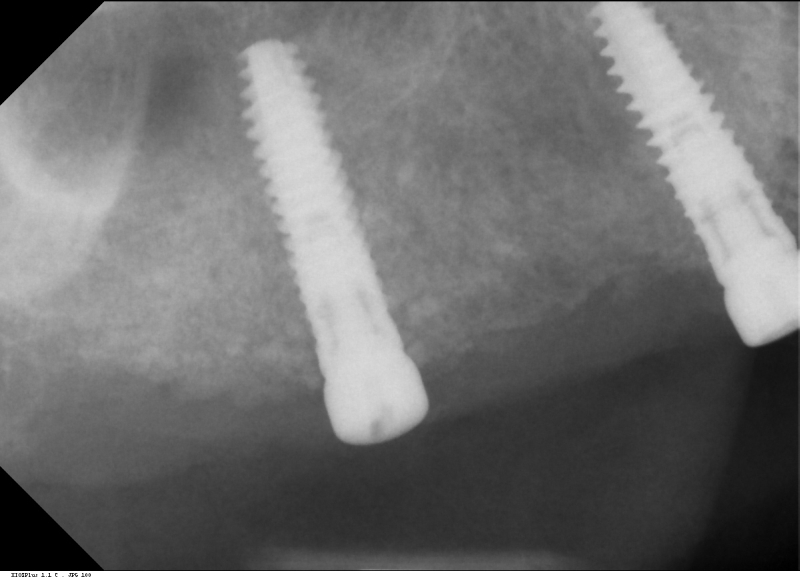

Initial x-ray showing bone loss around implants placed 5 years ago in another dental clinic